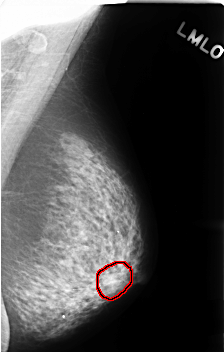

C_0419_1.LEFT_MLO

LEFT_MLO LINES 4576 PIXELS_PER_LINE 2904 BITS_PER_PIXEL 12 RESOLUTION 50 OVERLAY

FILE: C_0419_1.LEFT_MLO.OVERLAY

TOTAL_ABNORMALITIES 1

ABNORMALITY 1

LESION_TYPE MASS SHAPE OVAL MARGINS ILL_DEFINED

ASSESSMENT 3

SUBTLETY 3

PATHOLOGY BENIGN_WITHOUT_CALLBACK

TOTAL_OUTLINES 1

BOUNDARY